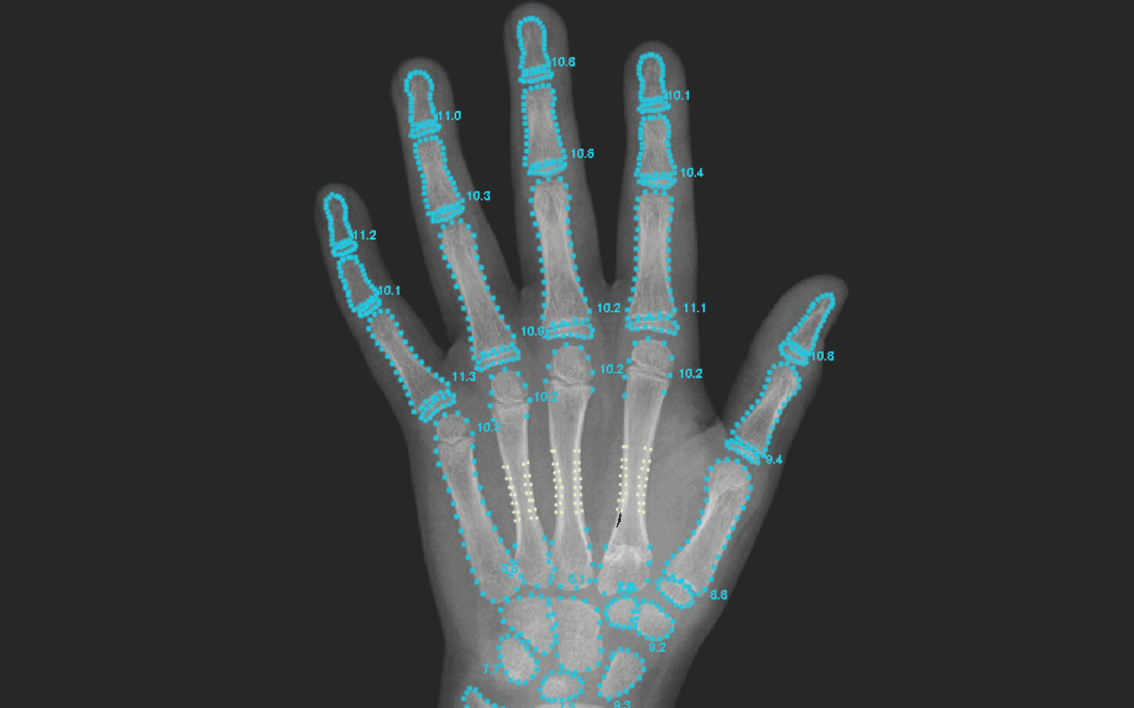

当院オリジナル開発

X線検査機器

お子様の成長評価に不可欠な「骨年齢」の測定にはX線検査が必要ですが、体への影響を気にされる保護者の方も少なくありません。

当院では、そうした声にお応えし、医師監修のもと独自に開発した低負担のX線機器を導入。一般的な装置に比べて身体への負担に配慮した設計となっており、安心して検査を受けていただけます。また、撮影は左手のみで行うため、影響を最小限に抑えています。

お子様の健康を第一に考えた、安全かつ高精度な検査体制で、安心して成長評価を受けていただけます。

REASON03 AI成長予測システムを導入

骨の成熟度を評価する「骨年齢判定」は、成長予測や診断において極めて重要な指標です。しかし従来は、医師の目視による判定であるため、評価にばらつきが生じる可能性がありました。

当院では、より高精度かつ客観的な診断を実現するため、世界中の医療現場で導入が進むAI骨年齢解析システムを採用。AIが骨の形状や成長状態を数値化し、数分で信頼性の高い骨年齢を自動解析します。

医師の専門的な判断にAIのデータを掛け合わせることで、より的確な成長評価・治療計画が可能となります。